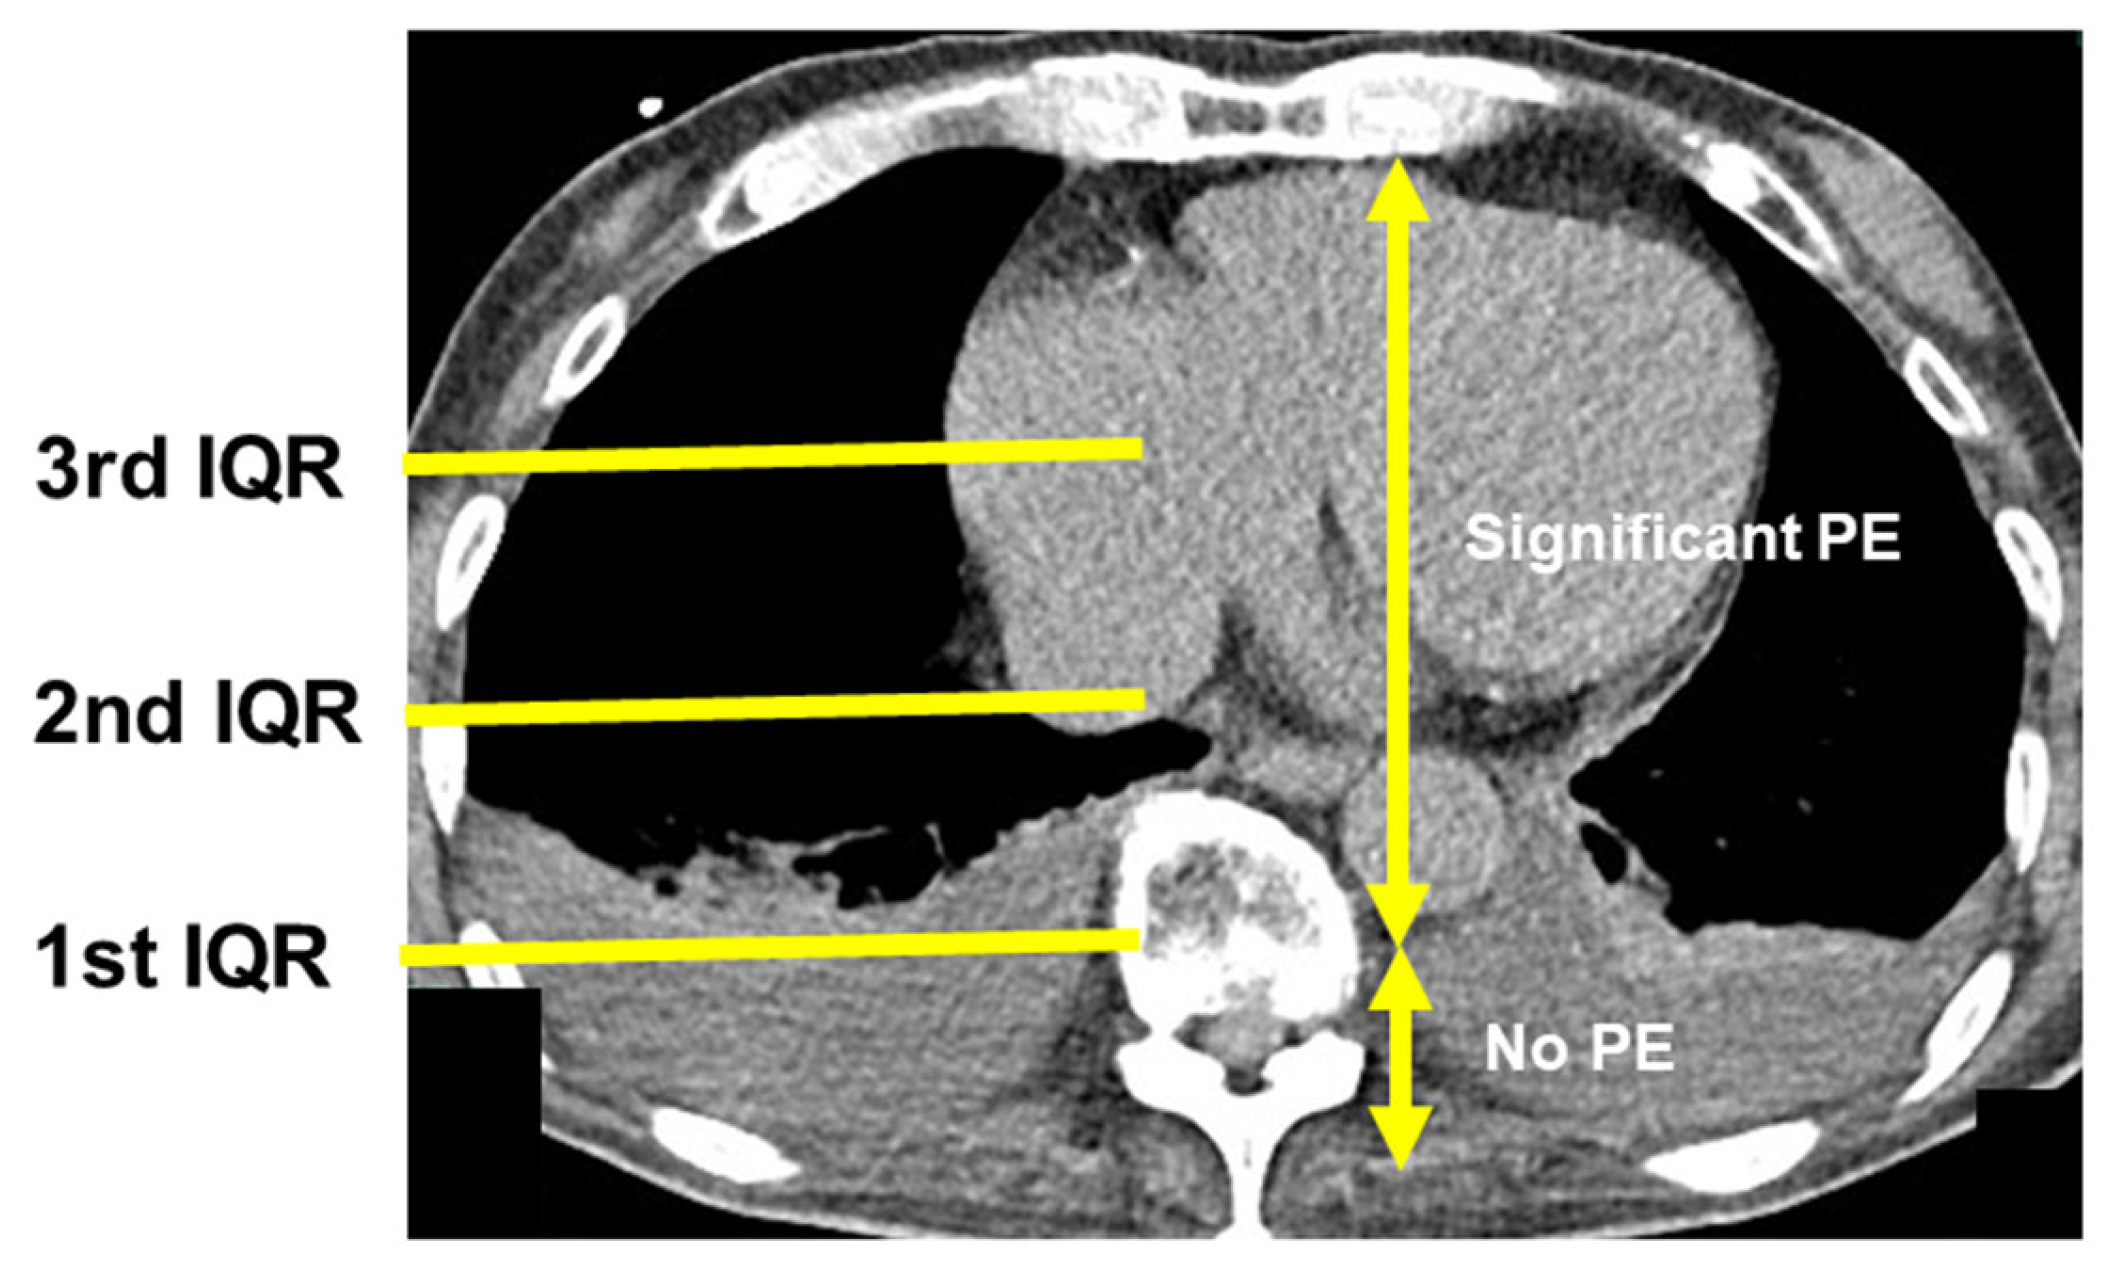

2.5. Chest Computed Tomography

3.2. Presence of PE